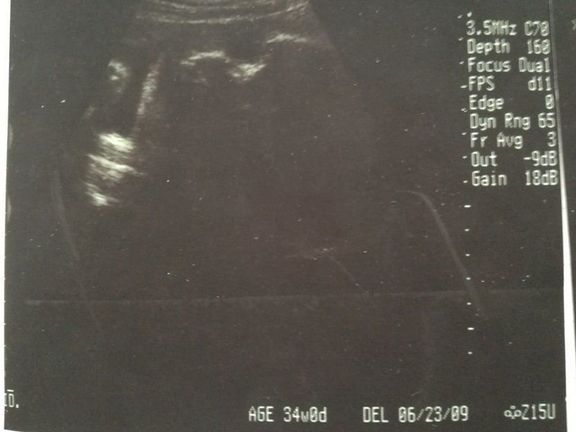

【応募すると全員もらえる】GELATO PIQUE エコー写真専用リフィルアルバム&エコー写真デジタルフレームが『初めてのたまごクラブ』冬号でもらえる!妊娠・出産

【応募すると全員もらえる】GELATO PIQUE エコー写真専用リフィルアルバム&エコー写真デジタルフレームが『初めてのたまごクラブ』冬号でもらえる!妊娠・出産 -

【応募すると全員もらえる】GELATO PIQUE エコー写真専用リフィルアルバム&エコー写真デジタルフレームが『初めてのたまごクラブ』秋号でもらえる!妊娠・出産

【応募すると全員もらえる】GELATO PIQUE エコー写真専用リフィルアルバム&エコー写真デジタルフレームが『初めてのたまごクラブ』秋号でもらえる!妊娠・出産 -